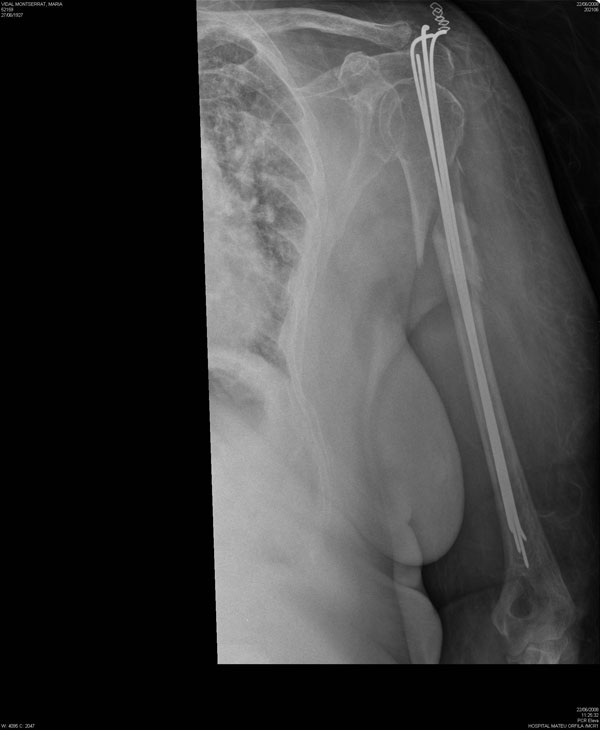

Fractura de húmero tras osteosíntesis con clavo gamma.